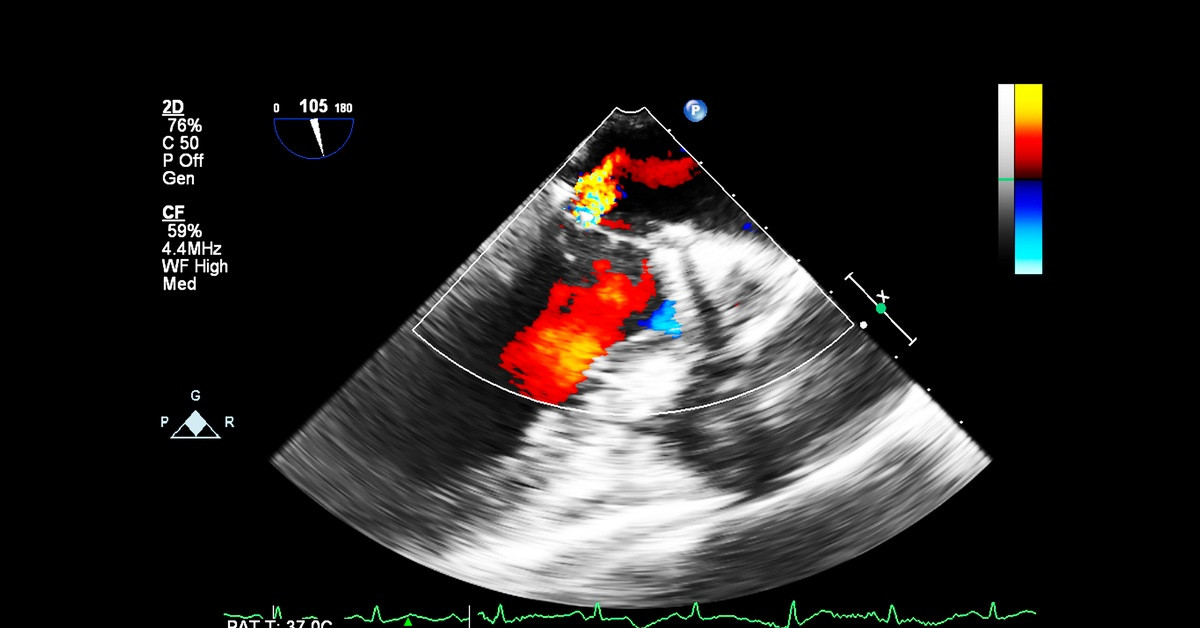

Doppler technology has become an essential diagnostic tool in modern medicine, enabling healthcare professionals to assess blood flow and cardiovascular function with remarkable precision. Exploring recent innovations in Doppler signal processing reveals how technological advancements continue to impact clinical capabilities and patient outcomes.

Contemporary Doppler systems incorporate sophisticated digital signal processing algorithms that enhance signal clarity and diagnostic precision. These algorithms employ advanced filtering techniques to eliminate background noise and motion artifacts that traditionally compromise signal quality.

The implementation of Fast Fourier Transform techniques enables precise frequency analysis, allowing clinicians to distinguish between arterial and venous flow patterns with greater confidence. Modern processors can simultaneously handle multiple frequency bands, providing comprehensive hemodynamic information from a single examination.

These technological improvements provide clear clinical benefits, enabling earlier detection of vascular abnormalities and more accurate assessment of fetal well-being. The computational power of current systems also supports real-time spectral analysis displays that provide immediate visual feedback during examinations.